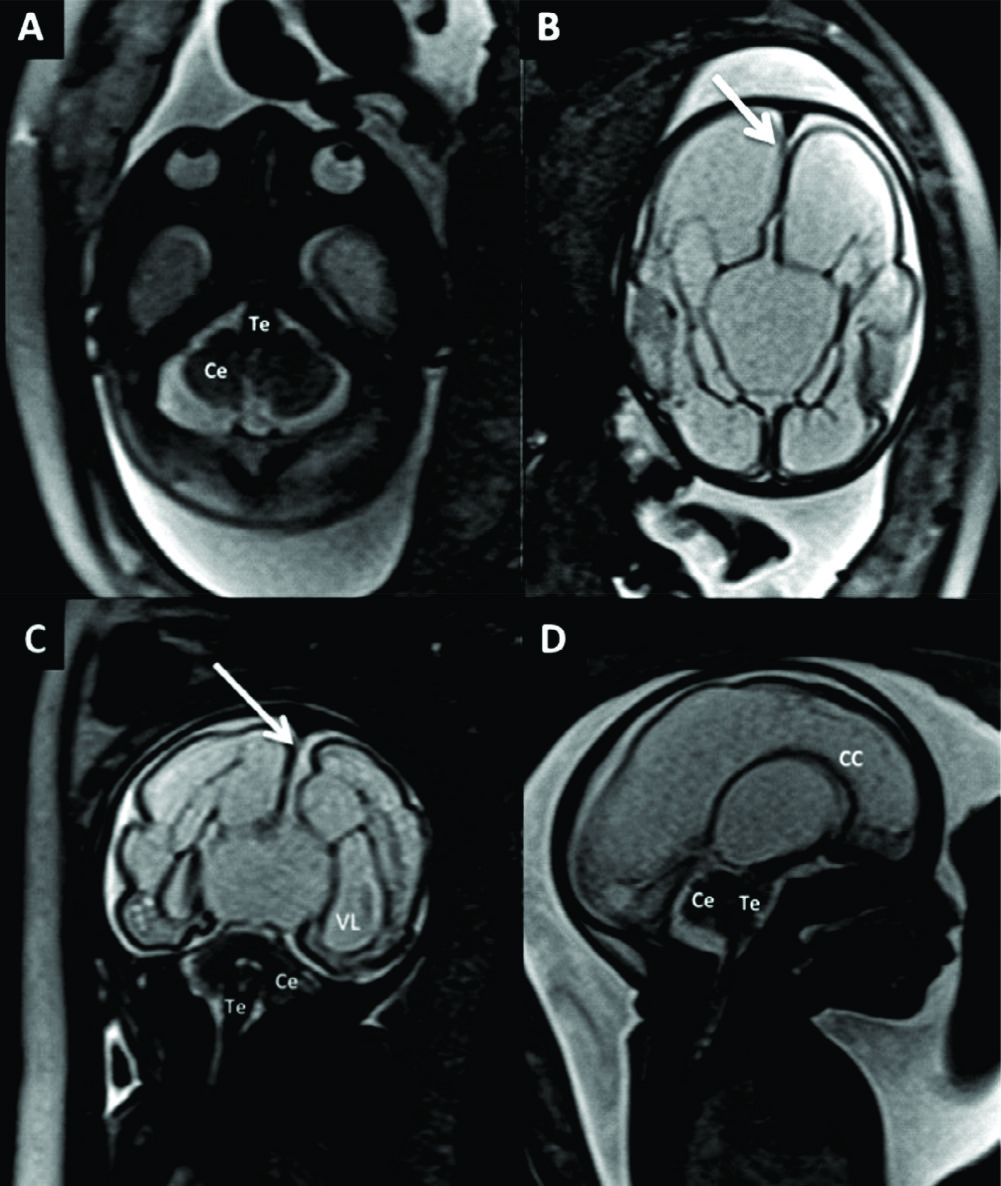

Figura 9

RM Fetal en Malformación de Fosa Posterior.

Se presentan 2 casos con diagnóstico de Dandy-Walker, ambos con malformación quística de la fosa posterior (è) comunicada con el IV ventrículo por alteración del desarrollo del vermis cerebeloso. En A y B imágenes sagital y axial de RMf realizada a las 27 semanas donde además se identifica dilatación del sistema ventricular supra-tentorial moderada. En el 2º caso (C y D) se observa una severa dilatación del sistema ventricular supra-tentorial con adelgazamiento del cuerpo calloso en un feto de 29 semanas de edad gestacional.

Te: Tronco encefálico

Ce: Cerebelo

Figura 10

RM Fetal en Malformación de Chiari.

Estudio realizado a las 29 semanas con diagnóstico ecográfico de mielomeningocele. En imagen coronal (A) se observa la severa dilatación del sistema ventricular supra-tentorial lo que se corrobora en la imagen axial (B) con una disposición colpocefálica de los ventrículos laterales (VL). En la imagen fetal sagital (C) se reconocen el cerebelo (Ce) y tronco encefálico (Te) sin identificarse claramente el IV ventrículo lo que indica una disminución de las dimensiones de la fosa posterior. En el mismo plano se observa el defecto de cierre posterior del tubo neural (è) con un saco de meningocele. La imagen axial a nivel de ese saco (D) muestra claramente el defecto espinal posterior (è) aunque sin observarse claramente el contenido neural del mismo.